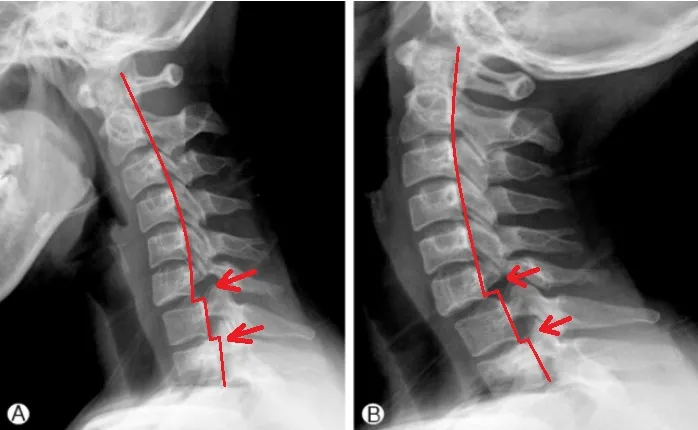

頸椎滑脫位於頸椎小面關節處,而滑脫顧名思義則是骨骼位置向前或向後移動到錯的位置,即姿勢不良、受到撞擊而改變於此關節位置情形者皆屬於高風險族群。

頸椎滑脫 的診斷方式有哪些?

X光檢查以及常見該神經症狀分布、症狀主述判斷